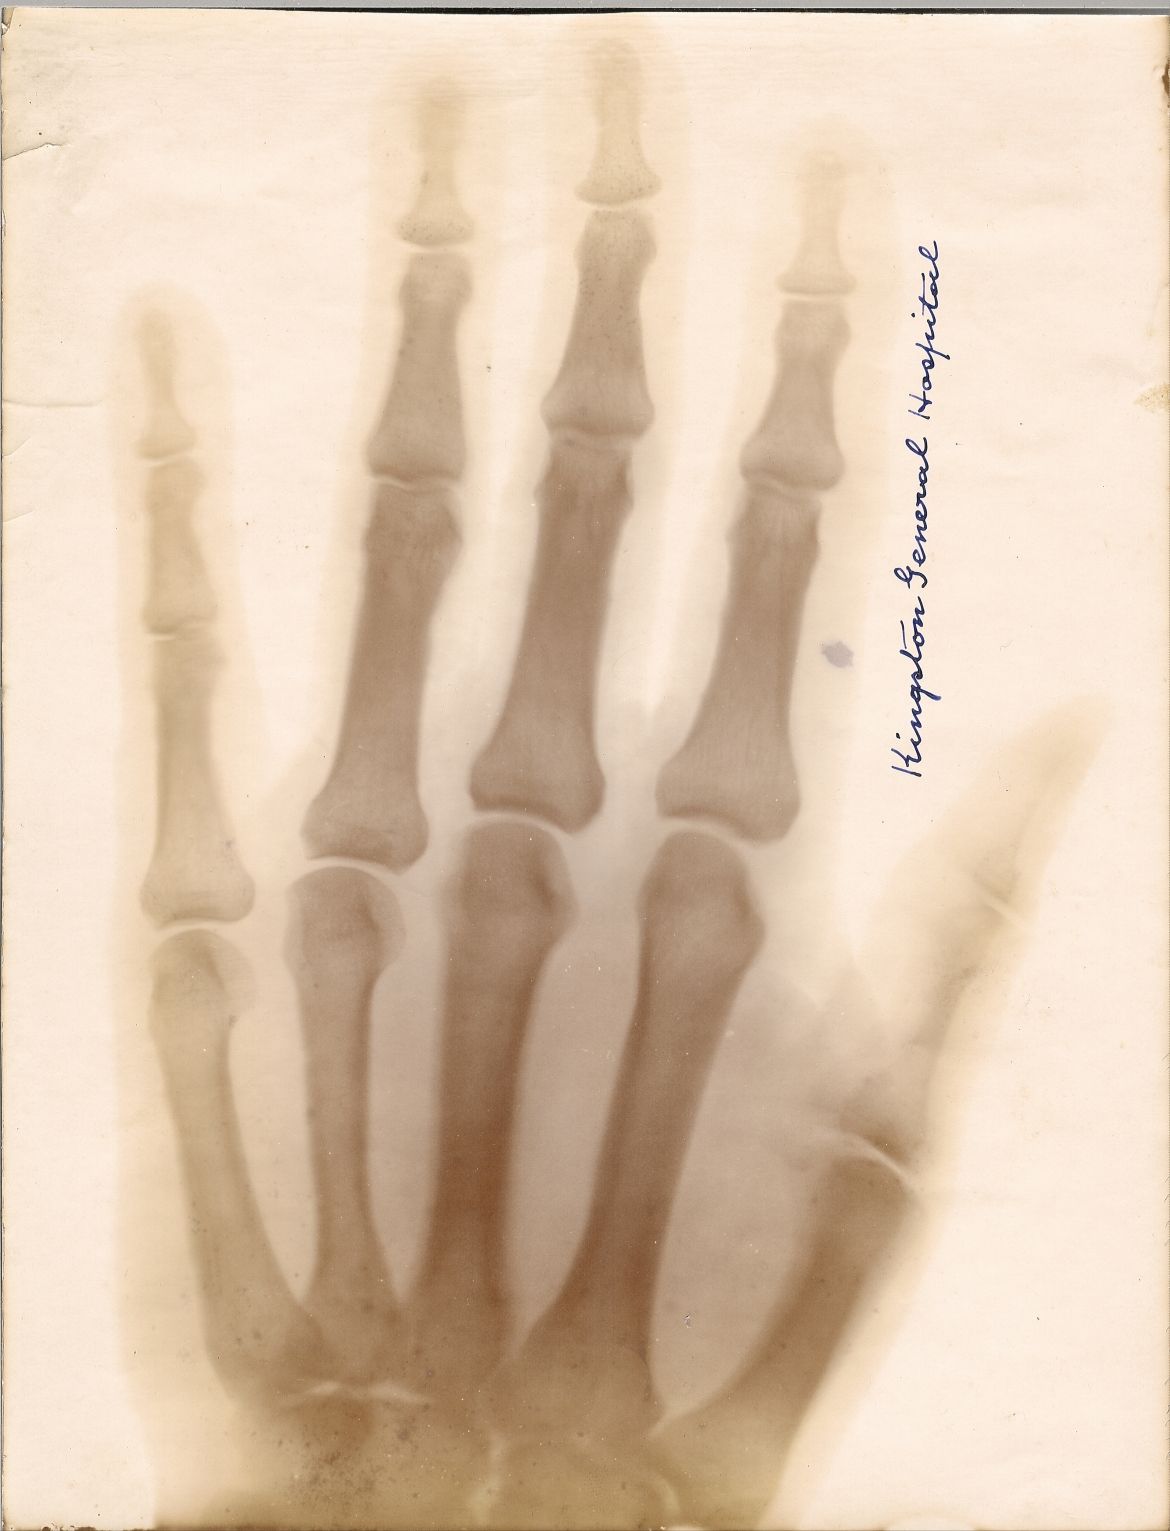

X-rays first made their appearance in Kingston on February 17, 1896, when the Weekly Whig reported that Captain John Bray Cochrane (1860-1946), Professor of Physics and Chemistry at the Royal Military College, had taken an x-ray image of the hand of Madame Emma Albani, a celebrated singer, as a demonstration.

Cochrane first applied the diagnostic power of the x-ray to a medical case in May of 1896. A patient named Miss Hooper had run a sewing needle into her palm, which subsequently became so swollen that physicians could not identify the location of the needle to extract it. Cochrane took two x-rays of the hand at RMC, each requiring 12 minutes of exposure, clearly identifying its location. Then, KGH surgeon Dr. R.K. Kilborn, was able to remove the needle.

Later that year, under Medical Superintendent Dr. James Third (1865-1925), KGH recruited Cochrane as the hospital’s first cathographer and acquired its own x-ray equipment. KGH became the second Canadian hospital to purchase x-ray apparatus for medical use and records suggest that patients travelled to Kingston from as far as Buffalo, New York to benefit from the technology.